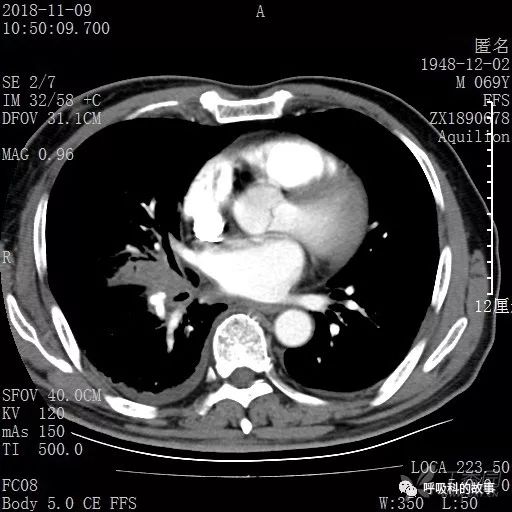

胸部增强CT示右肺门占位伴远端阻塞性肺炎,纵膈、右肺门、右侧颈根部、右侧腋下及肝门部肿大淋巴结。两侧胸腔少量积液。

肺窗CT